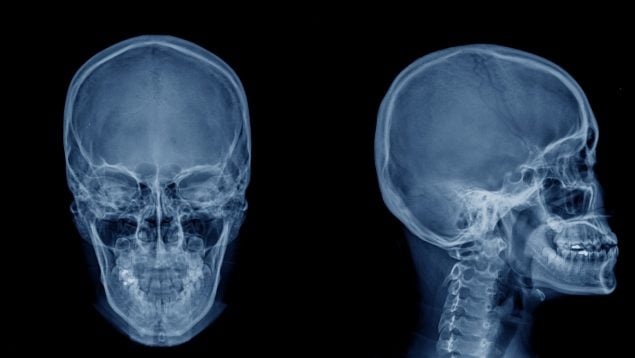

Y añade: «Tu organismo lo va acumulando, afectando principalmente el sistema nervioso, daño neuronal y estrés oxidativo, produciendo retraso cognitivo, problemas de atención, alteraciones de la memoria, disminución del coeficiente intelectual, alteraciones motoras y hasta alteraciones de lenguaje. Todo este daño aún es mayor en niños pequeños y en mujeres embarazadas».

El problema aparece cuando el consumo deja de ser ocasional y se convierte en un hábito diario. El mercurio, especialmente en su forma orgánica (metilmercurio), se acumula en los tejidos y afectar al desarrollo neurológico en el embarazo y la infancia.

Estos efectos son especialmente preocupantes en niños pequeños, porque su sistema nervioso aún está en desarrollo, y en mujeres embarazadas, ya que el mercurio puede atravesar la barrera placentaria y llegar al feto.

El mercurio puede presentar riesgos para la salud, especialmente porque afecta al sistema nervioso central en desarrollo. Esto puede ocurrir por exposición directa derivada del consumo de determinados alimentos o indirectamente, ya que el mercurio puede atravesar la placenta y también estar presente en la leche materna.